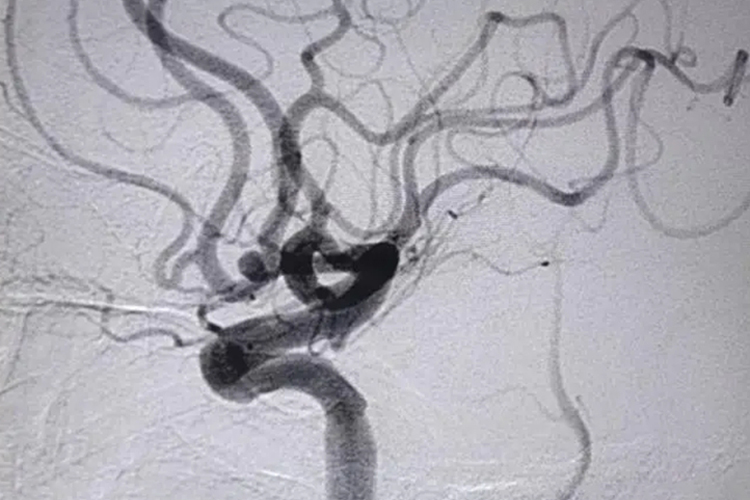

- 而脑血管造影,同样是DSA方式,价格大概在6000-10000元。